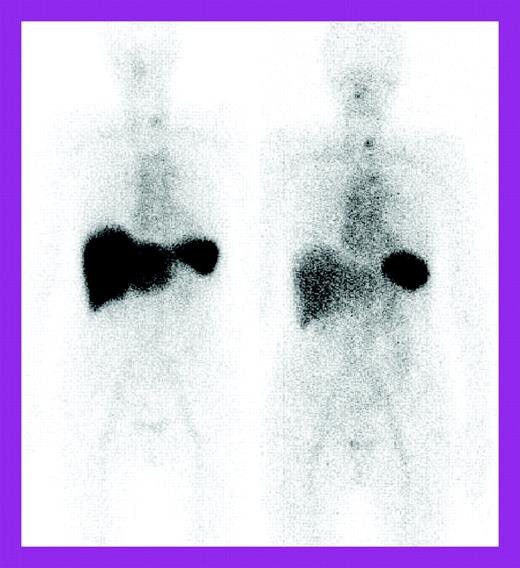

The study by Wechalekar and colleagues is a larger retrospective study of 75 patients treated with a risk-adapted regimen of cyclophosphamide, dexamethasone, and thalidomide and followed at the National Amyloidosis Centre, United Kingdom, with 123I–serum amyloid P component (SAP) scintigraphy as well as the usual light chain measurements. These patients were considered ineligible for high-dose chemotherapy by British guidelines.4 The 74% clonal response rate was impressive for a nontransplantation regimen, but organ responses lagged behind at 27%. 123I-SAP scans showed regression of liver deposits in responding patients (see the figure) but less often, decreases in kidney deposits. Fewer patients had significant adverse effects; treatment-related mortality occurred in 4%. However, the patients represented only 4.8% of those seen at the Centre over 5 years, raising the question of possible selection bias, although patient characteristics were similar to those described in the other 2 studies, except that severe autonomic or peripheral neuropathy patients were excluded.

Serial 123I-labeled anterior whole-body SAP scintigraphy. See the complete figure in the article beginning on page 457.